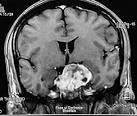

En radiografías simples, el cordoma aparece como una lesión solitaria con destrucción ósea en la línea media. Frecuentemente esta lesión es acompañada por masas en el tejido blando. Calcificaciones focales están presente en la mitad de los casos. Estudios de TAC y RNM ayudan en la identificación del componente de tejido blando, calcificaciones y extensión epidural. La identificación de recurrencias locales se hace por medio de RNM. En rastreo de hueso el cordoma presenta adquisición/absorción reducida.